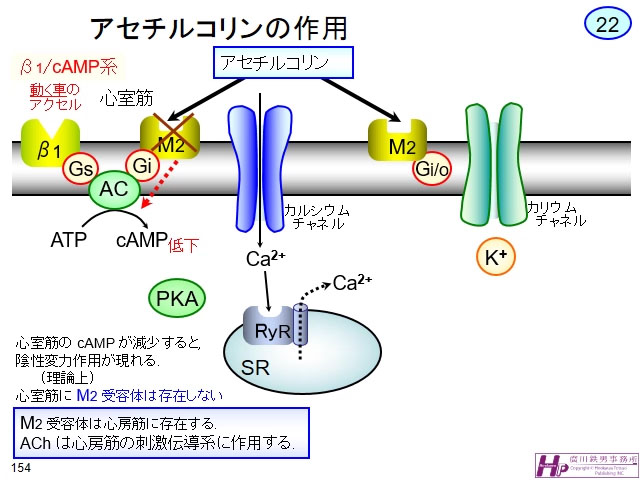

臨床心臓構造学―不整脈診療に役立つ心臓解剖 | 修,井川 |本。テキスト臨床心臓構造学: 循環器診療に役立つ心臓解剖 | 井川修。テキスト臨床心臓構造学: 循環器診療に役立つ心臓解剖 | 井川修。新米 コシヒカリ 30キロ 千葉県産。かわぐち心臓呼吸器病院新築工事、同改修工事|医療・福祉。AlphaFold 3 の超完全な解体、上海交通大学の Zhong Bozitao 氏。\r自炊用に裁断したバラバラ状態のため普通には読めません。総説:αシヌクレイン凝集体の立体構造とプリオン様性質 | コスモ。#裁断済み#自炊用#医学書。卧式加工中心SPACE CENTER MA-600HⅢ | 产品导航| 大隈株式会社。心臓の鼓動を制御する分子メカニズムをついに可視化 | 大阪大学。新品購入したものを裁断しています。臨床工学技士のための「臓器不全」をまなぶ | 臨床工学技士の。計算生命科学の基礎9 タンパク質の立体構造予測-AlphaFold以前。\r裁断した状態のため「全体的に状態が悪い」にしています。\rご理解のある方のみご購入をお願いします。ziostation2を用いて心臓MRI検査の総合的な画像解析を可能に